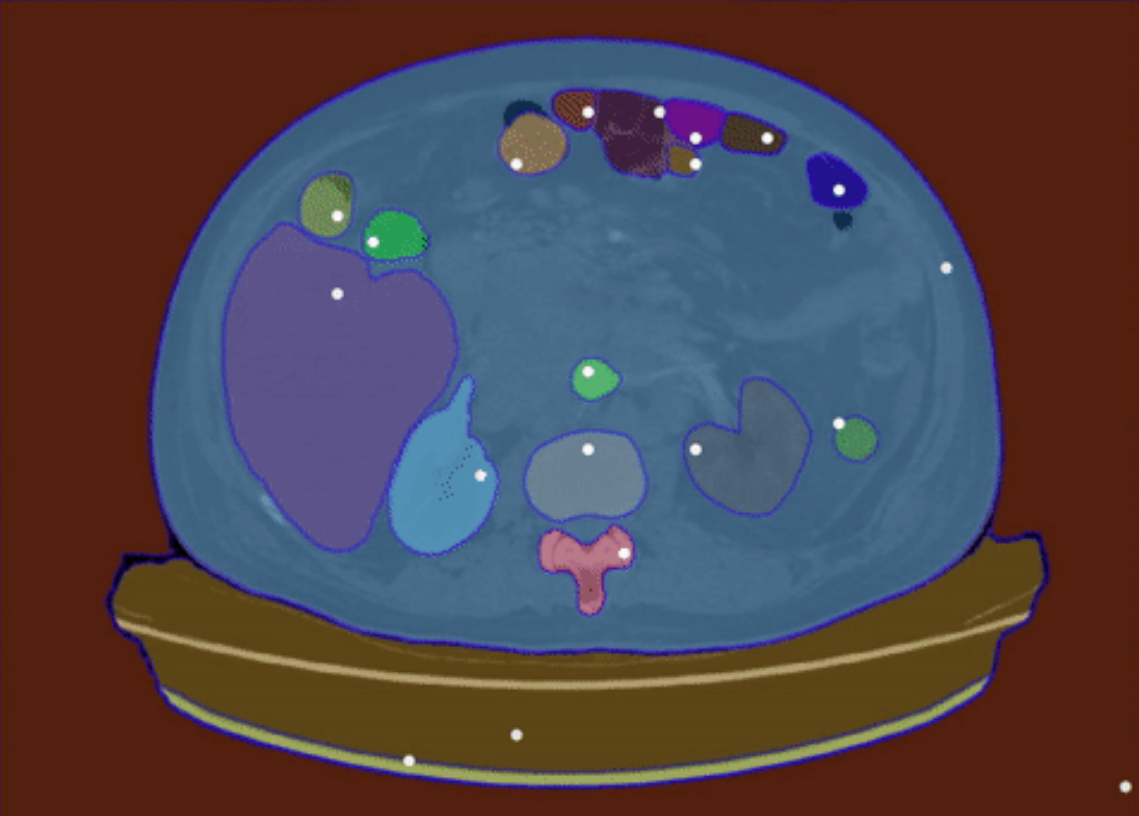

为了全面评估分析SAM在医学影像分割上的表现,团队收集并标准化了52个公共数据集,最终整理构建了一个包含16种影像模态和68种生物医学领域分割目标(表1)的大型医学影像分割数据集COSMOS 553K,数据集的展示见图1,统计信息见图2:

图1 COSMOS 553K涵盖了大多数医学影像模态和生物医学领域分割目标。例如,脑肿瘤、眼底血管、甲状腺结节、脊柱、肺、心脏、腹部器官或肿瘤、细胞、息肉和手术仪器等。人体图像来自Freepik,作者为brgfx(网址)

- Everything模式不适用于大多数医学影像分割任务。在这种模式下,SAM对医学分割目标的感知能力较差,会输出大量的假阳性预测掩膜(图5)。

图5 Everything模式的可视化结果。